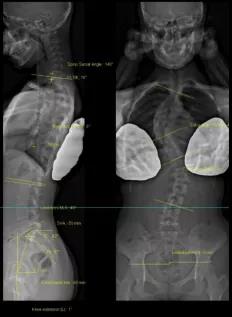

法國EOS X射線影像采集系統(tǒng)

?諾貝爾物理學獎的新型X射線探測技術;

?實現(xiàn)了人體1:1真實成像;

?是非拼接全脊柱、全下肢一次性成像X線設備;

?僅需0.05mSv(約一張胸片的劑量)即可完成全脊柱正側位成像。

臨床應用及優(yōu)勢:

?正側位全長影像一次掃描成像的優(yōu)點:負重位正交同步拍攝、線性掃描1:1全長片、動態(tài)自動增益控制;

?雙球管正側位同步拍攝:一次掃描同時獲得正、側位影像,消除兩次拍攝的系統(tǒng)誤差;

?精準的線性掃描:幫助醫(yī)生對脊柱、關節(jié)等相關骨骼疾病進行術前診斷、制定手術計劃、評估手術效果、跟蹤隨訪以及相關科研工作;

?不失真高質量圖像:全身視圖1:1。

案例圖

脊柱側彎